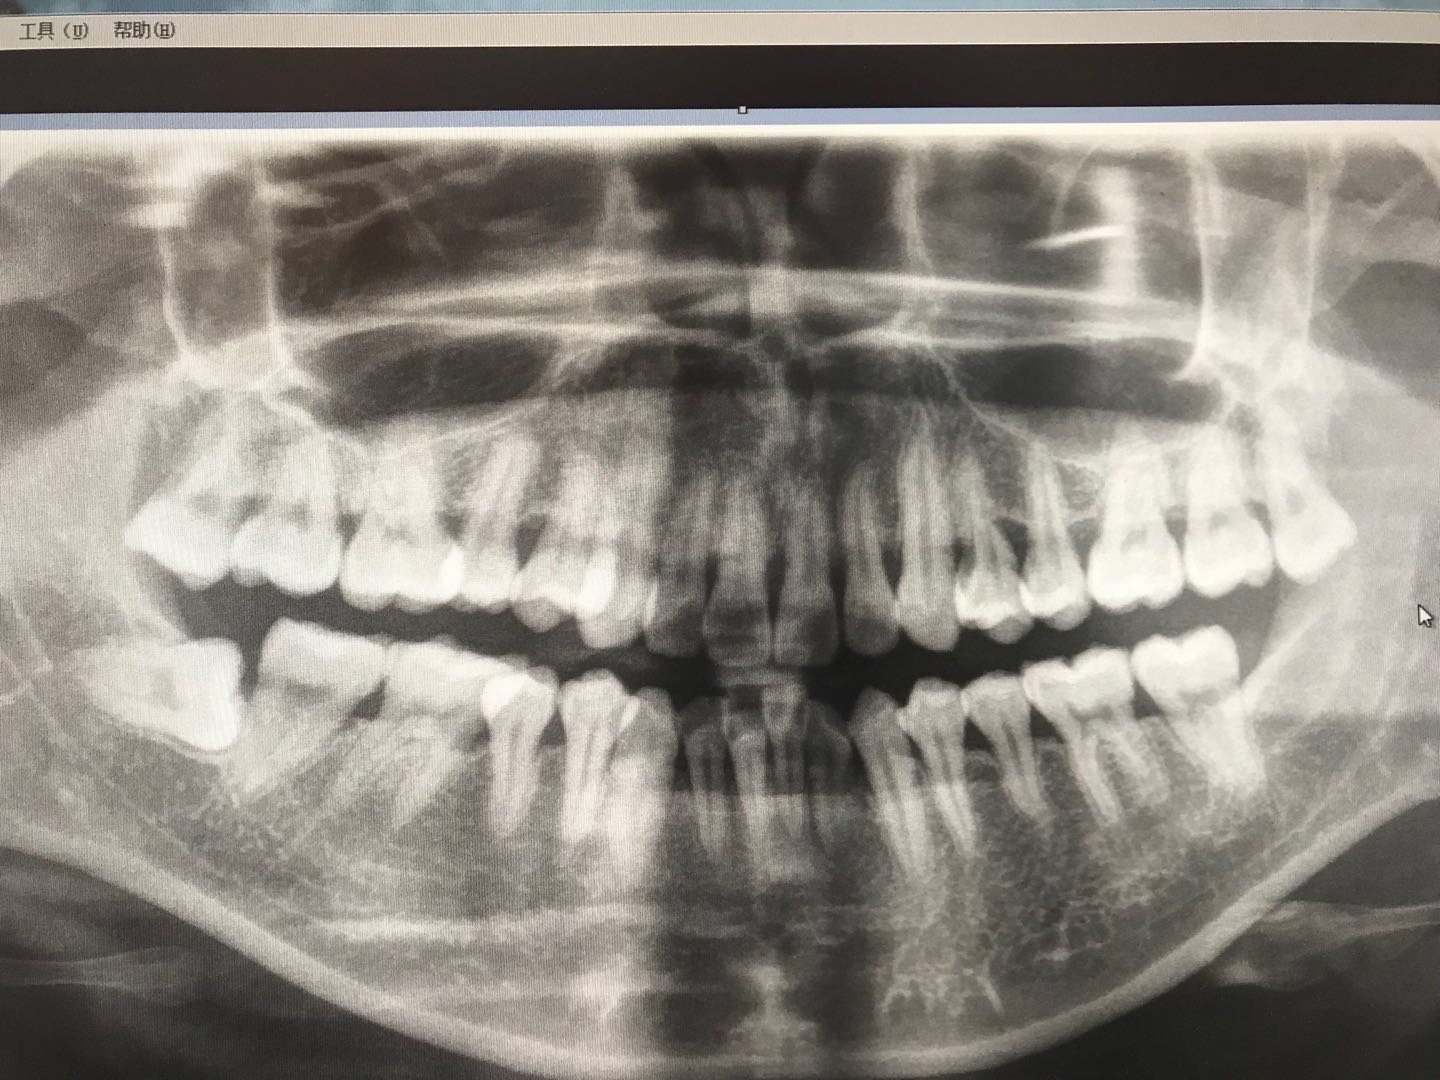

查体:48近中低位埋伏阻生,牙体露出少许,叩-,无松动,冠周牙龈无明显红肿,无压痛,开口正常。 辅助检查:曲片示48近中低位水平阻生,根尖近下颌神经管,根尖无明显暗影。

诊断:48低位水平阻生 治疗方案:建议拔除48,告知注意事项及风险,签知情同意书。 治疗:48局麻下(利多卡因,阻滞,4ml,碧蓝,浸润,0.8ml),切开,翻瓣,高速反角手机去除近中阻力,然后拔除余下牙根,清理牙槽窝,填塞止血海绵,缝合,棉球压迫止血,冰敷,一周拆线,全身抗炎,交待术后注意事项…,不适随诊。

术后回访效果良好,脸无明显肿胀,疼痛正常。 讨论:对于下颌低位水平埋伏阻生牙的拔除,术前一定要拍牙片,了解牙齿形态及方向,了解牙根的形态及与下颌神经管的关系;告知患者情况及风险,签署知情同意书。局麻下要打到位,习惯加一点碧蓝减少出血,开阔视野。操作前,分析阻力,核对牙位,然后再一步步的去除阻力,动作轻柔,最后拔除患牙,清创缝合,术后注意事项的交待及回访!